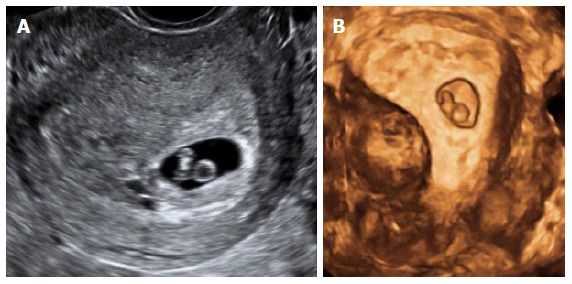

Фото Второй Беременности

Фото Второй Беременности 117 фотографий